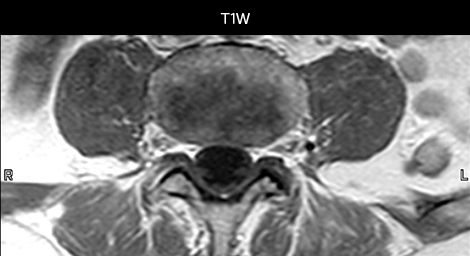

“We use mDIXON TSE extensively in our spine imaging in the emergency room,” says Dr. Karis. “It’s particularly nice in that it is very robust with regard to susceptibility type of problems that would come up with traditional spectral fat-saturated images; these problems are essentially eliminated with the mDIXON technique. In our ED environment it’s really nice to have the fat-free imaging that goes along with the mDIXON technique.

“For the thoracic and cervical spine routine non-contrast exam, for example, we perform one mDIXON T2 TSE sequence, which provides us with two outputs: the fat-and-water-together T2-weighted images, as well as the water-only sagittal T2-weighted images. And then we also perform an axial gradient echo exam.”

To minimize the time taken to perform scans, rapid MRI examination protocols (ExamCards) were developed, shortening the total scanning time to even less than 10 minutes in some exams. Techniques like mDIXON (modified DIXON) are used for robust capturing of fat-free MRI images in a hectic ED environment.